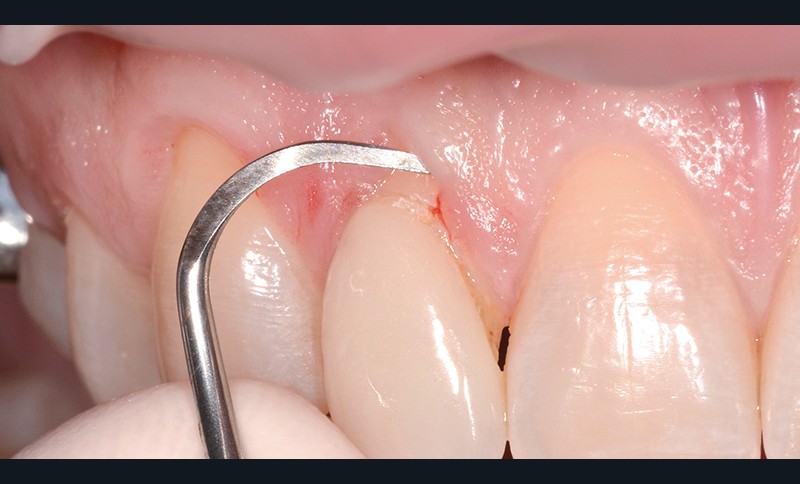

bibli/1.31.jpgAprès les anesthésies, le site est cureté manuellement.

bibli/1.3.31.jpgMicrolame angulée, pas d'incision croisée de la papille.

bibli/1.3.jpgIncisions sulculaires dans le site receveur à la microlame sans sectionner les papilles.

bibli/1.3.jpgIncisions sulculaires dans le site receveur à la microlame sans sectionner les papilles.

bibli/1.31.jpgAprès les anesthésies, le site est cureté manuellement.